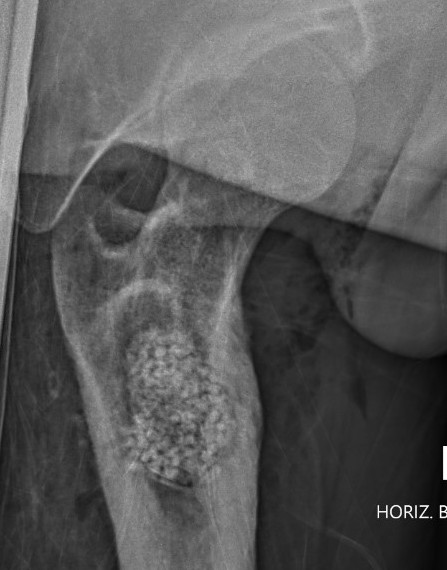

X-ray

Long bone

- more common meta-diaphyseal

- large faintly radiolucent lesion

- thin reactive rim

- may be expansile